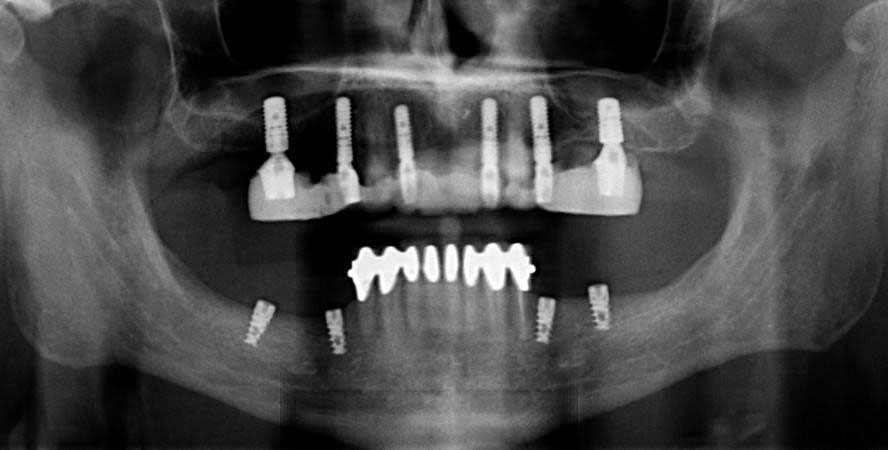

For patients who are missing most or all of their teeth, the All-on-X technique offers a life-changing solution. This innovative approach uses as few as four to six strategically angled implants to support a complete, fixed arch of teeth. Unlike traditional dentures, an All-on-X restoration is permanently secured to the implants and does not need to be removed for cleaning. Patients enjoy a full set of beautiful, functional teeth that feel remarkably natural. Dr. Tran will work closely with you to determine whether All-on-4, All-on-5, or All-on-6 is the right approach based on your bone density, anatomy, and personal goals.